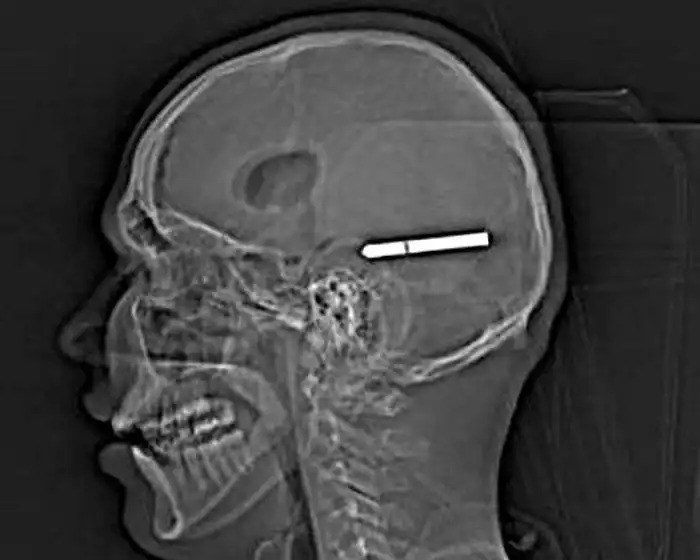

Необычные предметы в теле людей на рентгеновских снимках

На рентгеновских снимках людей порой можно обнаружить самые необычные предметы, которые находятся в их теле.